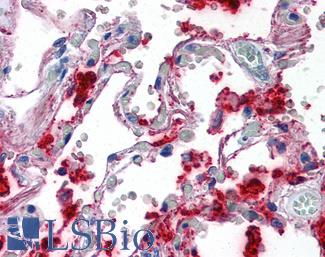

Surfactant Protein A (SFTPA1)

Anti-SFTPA1 / Surfactant Protein A antibody IHC of human lung. Immunohistochemistry of formalin-fixed, paraffin-embedded tissue after heat-induced antigen retrieval. Antibody LS-B2543 concentration 10 ug/ml.